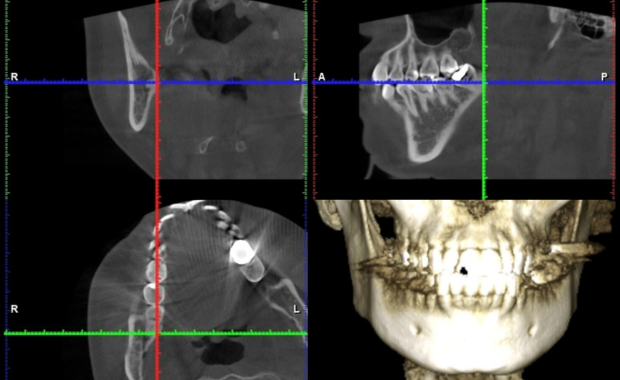

歯科用CT

パノラマレントゲンでは見えにくい「立体的な構造」を把握するために使用します。顎の骨や神経の位置を3Dで確認でき、インプラントや根管治療、難しい親知らずの抜歯などで欠かせません。安全な治療を行うために、必要な場合に撮影します。